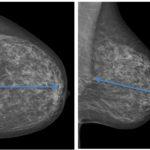

posicionamiento, proyección OML Y CC.

Las proyecciones principales son la oblicuo-medio-lateral (OML) y la cráneo-caudal (CC), para incluir la mayor cantidad de tejido mamario.

Fig 1 a y b: Mamografía.Proyección CC (a). Proyección OML (b). Posicionamiento adecuado. La distancia del pezón al pectoral debe ser similar.